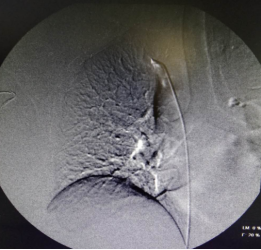

DSA下行血管造影+上腔静脉穿刺+置入长期透析导管手术过程(白色粗箭头所指用经皮血管穿刺套件进行上腔静脉穿刺过程)

血液净化中心医生制定了内瘘结扎方案,把人为建立血流回心的“高速公路”封堵,DSA引导下穿刺上腔静脉置入一根23cm的长期透析导管,手术难度很大。